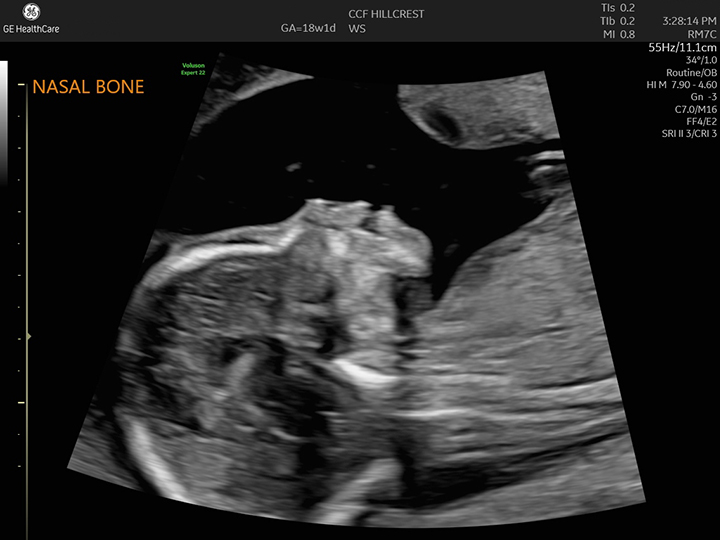

TIFFA stands for Targeted Imaging for Fetal Anomalies. It is a detailed anomaly scan done during the second trimester, usually between 18 and 22 weeks of pregnancy.